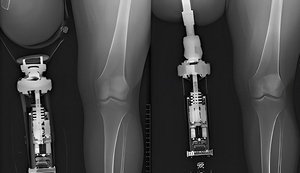

Минулого тижня в Міністерстві охорони здоров'я України пройшла конструктивна нарада щодо остеоінтеграції. Це імплант, який фіксується прямо в кістку, що дає можливість повноцінно використовувати протез захисникам та захисницям, які мають дуже високі ампутації.

Перше – як визначити, кому потрібні ці унікальні операції – наказ МОЗ, за яким зараз відбувається остеоінтеграція, показав свою ефективність – понад 95% остеоінтеграцій є успішними, а захисники і захисниці почали повноцінно ходити чи користуватися протезами рук.